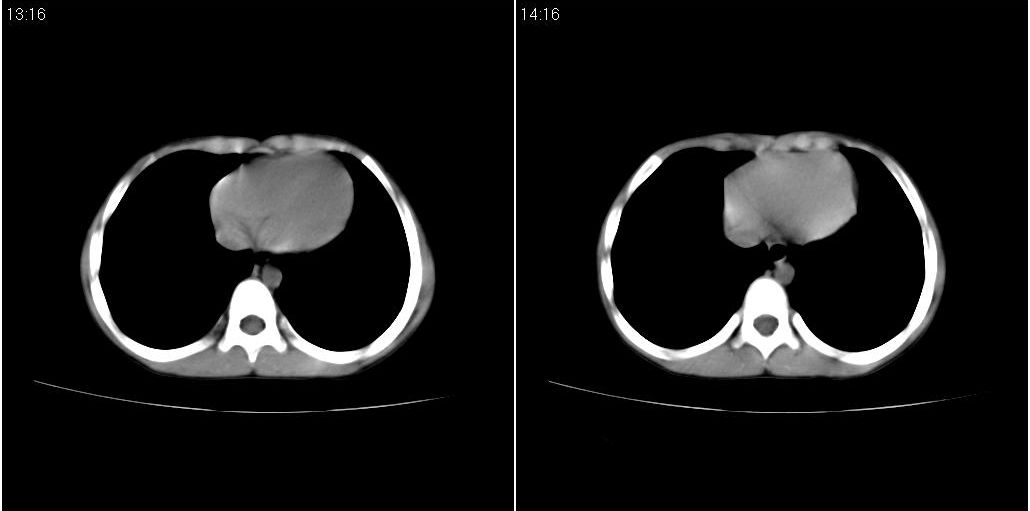

9月20号ct检查情况:

右上肺有班片状条索状高密度影。右肺上叶支气管稍变窄。右前上纵隔有结节状软组织密度影。上腔静脉旁淋巴结肿大。病灶抗炎后扩大。考虑结核可能性大。

右上肺不均匀密度增高,体积变小,水平裂弧状上移,纵隔内有肿大的淋巴结。考虑:

1、右上肺炎(吸收期),纵隔淋巴结肿大压迫右上叶肺膨张不全

2、纵隔淋巴结结核不能排除